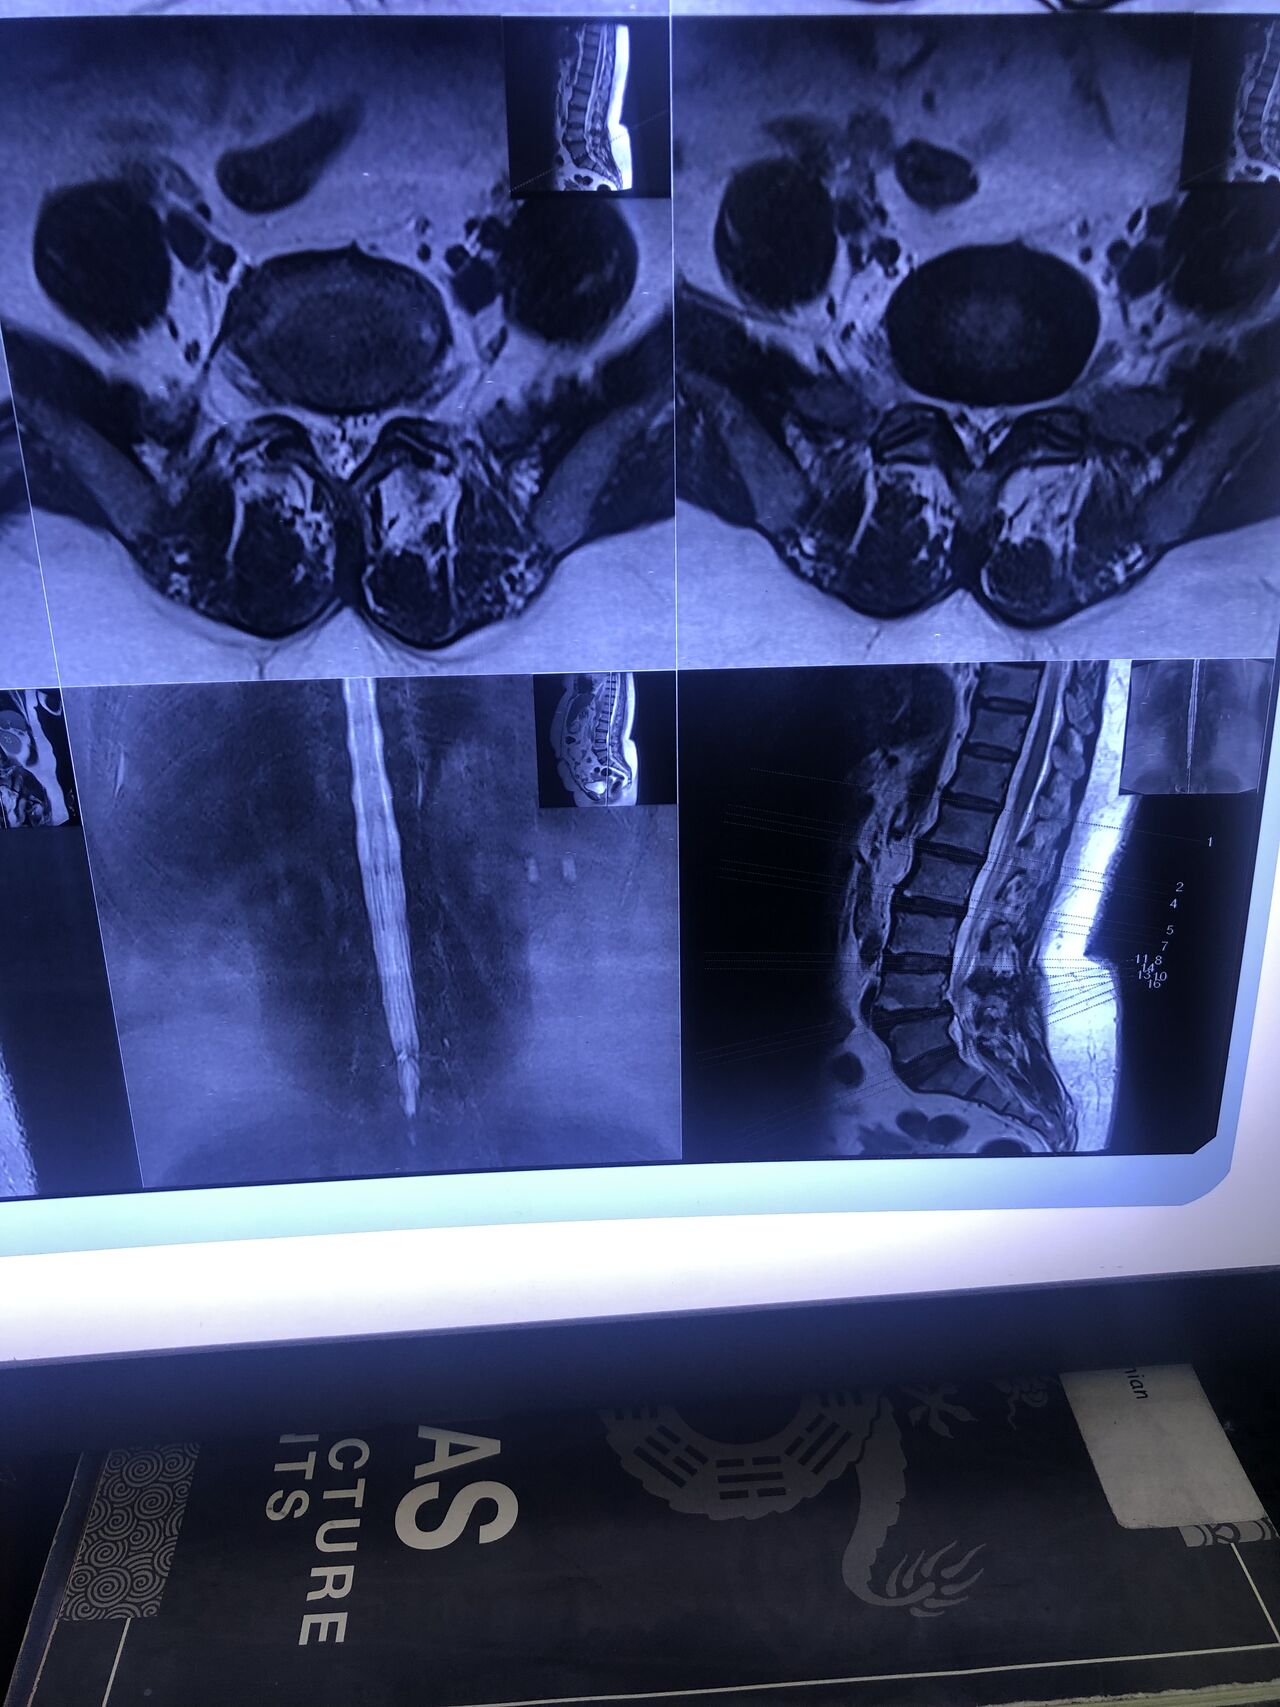

46 years old female patient presented to my clinic yesterday june 1/2025 with LBP and radicular L leg pain for several months which hasn’t responded to physio 2 neurosurgeons have visited her and didn’t suggest any surgery Neurological exam was unremarkable please see her mri/ emg/ncv and her huge tarlov cyst and possible L IVF L4-5 hyperbulge I ordered sacrum mri and ct scan and new emg/ncv and asked her with her sacral Ct scan and MRI first sees another two famous neurosurgeons and see if that large cyst is the reason for her pain if not i can work on her L4-S1 area Do you think her radicular pain can originate from her large cyst in sacrum? Do you consider surgery and removing her sacral cyst?